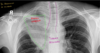

¿Qué patrón es el siguiente?

atelectasia

morfología de una atelectasia

triangular con base hacia la pleura y vértice hacia íleo o morfología lineal, ocasionando una retracción de estructuras

¿Qué lesión provoca la atelectasia sobre el parenquima y que estructura anatómica es importante buscar para sospechar el dx?

Ocasiona una retracción de estructuras Buscar tráquea.Ocasiona una retracción de estructuras Buscar tráquea

¿Qué patrón puedes ver?

atelectasia de morfología líneal